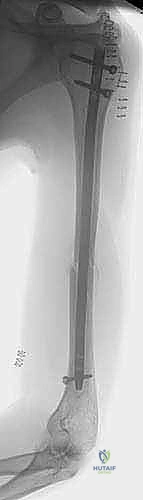

التثبيت بالمسمار النخاعي الأمامي: المعيار الذهبي الحديث

يُعد "المسمار النخاعي الأمامي" (Antegrade Nailing) - أي الذي يتم إدخاله من جهة الكتف نزولاً نحو الكوع - قمة التطور في علاج كسور منتصف وأعلى عظم العضد. تعتمد هذه التقنية على مبدأ "التثبيت البيولوجي" (Biological Osteosynthesis). بدلاً من فتح الذراع بالكامل لترتيب قطع العظم بدقة هندسية (مما يقتل التروية الدموية)، يتم إدخال سيخ معدني قوي (مصنوع من التيتانيوم المتوافق حيوياً) داخل تجويف العظم ليعمل كدعامة داخلية، مع ترك الكسر المفتت في بيئته الدموية الطبيعية الغنية بالخلايا الجذعية لتلتئم بسرعة.

5. إدخال المسمار النخاعي (Nail Insertion):

يتم اختيار مسمار التيتانيوم بالطول والقطر المناسبين اللذين تم قياسهما مسبقاً، ويتم إدخاله بلطف فوق سلك التوجيه حتى يعبر منطقة الكسر ويستقر في مكانه المثالي.

6. القفل الديناميكي والاستاتيكي (Locking):

لمنع المسمار من الدوران أو الانزلاق، يجب تثبيته ببراغي عرضية. يتم إدخال البراغي العلوية في الكتف عبر جهاز توجيه متصل بالمسمار. أما البراغي السفلية (فوق الكوع)، فتتطلب مهارة فائقة؛ حيث يتم إدخالها عبر شقوق صغيرة جداً (1 سم) باستخدام تقنية "اليد الحرة" (Freehand Technique) تحت توجيه الأشعة، مع حماية العصب الكعبري والأوعية الدموية بدقة.